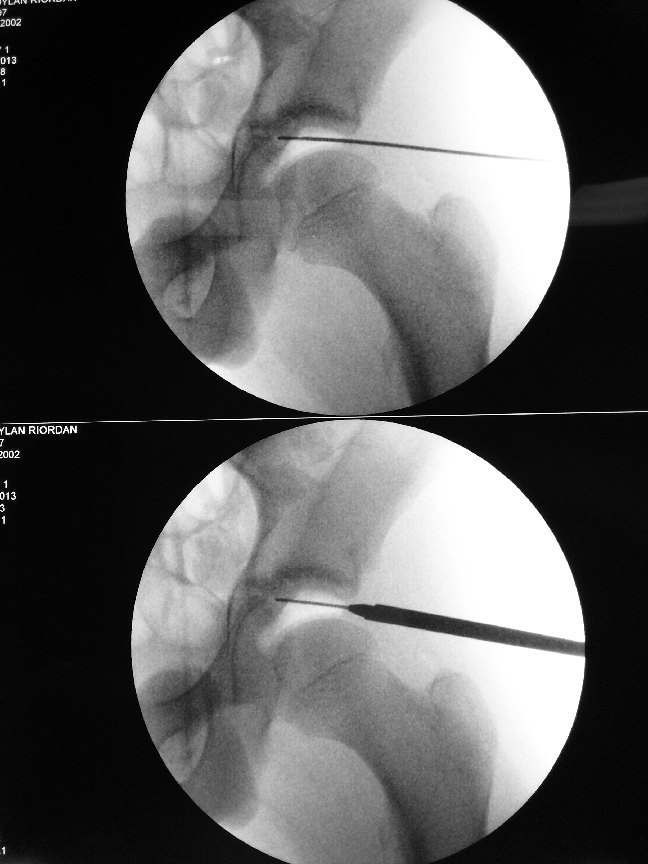

It is important to culture the causative bacteria before starting antibiotics.

Surgery to wash out the infected hip joint is often necessary and should be done as an emergency once the diagnosis is confirmed.

I prefer to perform a keyhole procedure to treat the infection in the hip. This involves hip arthroscopy.

Two tiny holes are created to allow visualisation of the inside of the hip joint.